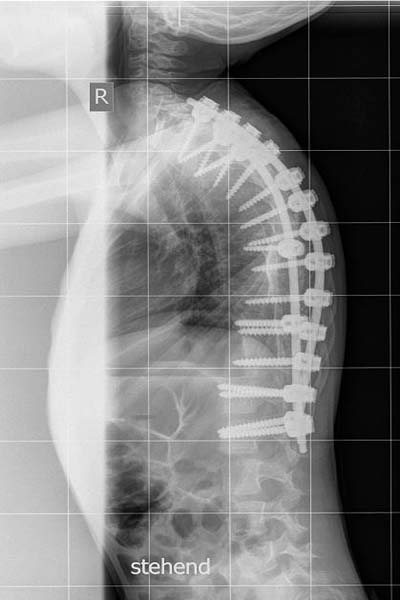

Luca hat seit längerem eine starke Wirbelsäulen-Verkrümmung ("linkskonvexe Kyphoskoliose").

Nachdem es zu Beginn hieß, es sein keine Korsett nötig/möglich, verschlimmerte sich diese Ende 2005 / Anfang 2006 so sehr (bis auf über 50°), dass wir etwas unternehmen mussten.

Die Verkrümung betrug inzwischen 108 Grad.

Dr. Hoffmann aus Leonberg riet uns daher zu einer Operation in Neustadt/Holstein an der Ostsee in der Klinik für Wirbelsäulenchirurgie mit Skoliosezentrum bei Professor Halm.

Am 4.9.2009 reisten wir dann nach einer Zwischenübernachtung in Hamburg zur Aufnahme an.

Am 8.9.2009 fand dann die OP statt. Die Verabschiedung vor der OP-Schleuse war der härteste Moment. Man übergibt sein Kind, das "nur" einen krummen Rücken hat und weiß nicht, wie alles nach dem Eingriff sein wird.

Lucas Wirbelsäule wurde von Th2 bis L2 versteift. Die Skoliose konnte bis auf 28 Grad reduziert werden.

Die Kyphose ist ebenfalls weniger stark ausgeprägt.

Luca ist deutlich aufgerichteter. Ein Korsett ist nicht mehr notwendig. Er ist daher mobiler und trotz der Versteifung erstaunlich beweglich.